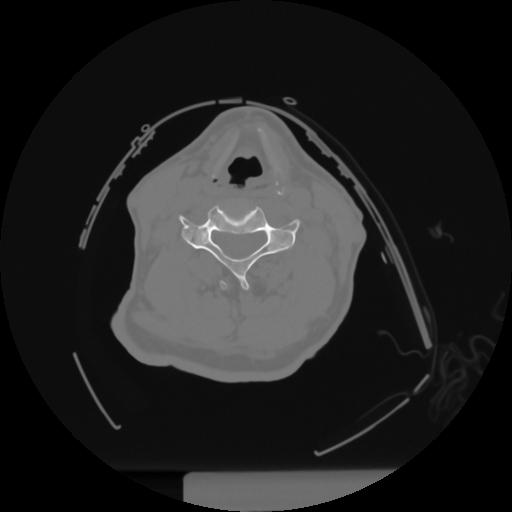

12 P.BLANDAS,,Vol,0.5,P.BLANDAS,,